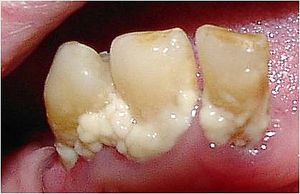

치아 우식증(충치)은 주로 뮤탄스 연쇄상구균에 의해 발생하는 감염성 질환으로, 치아의 에나멜이 산에 의해 부식되고, 더 나아가 내부 상아질까지 파괴될 수 있다.[1] 치태 내 세균 군집은 주로 산을 생성하고 산에 강한 종(예: 뮤탄스 연쇄상구균, 유산균)으로 구성되며, 비슷한 특성을 가진 다른 종도 관련될 수 있다.[31]

치태 내 세균은 음식물의 당질을 대사하여 산을 생성한다. 이 산은 치아 표면을 탈회시켜 충치를 유발한다.[1] 음식 섭취 후 잠시 동안 치태의 pH (수소 이온 지수)는 치아 탈회의 임계 pH (일반적으로 5.5 전후) 이하로 떨어진다. 이는 치태를 구성하는 충치 원인균이 음식의 당질을 대사하여 산으로 바꾸기 때문이다.

타액은 산을 중화하고 치아의 재광화를 돕는 역할을 하지만, 치태가 두껍게 쌓이면 타액이 침투하기 어려워 산을 중화하거나 치아를 재광화하는 효과가 떨어진다. 타액의 작용에 의해 수십 분 후에는 pH가 임계 pH 이상으로 회복되는데, 이를 재석회화라고 한다.